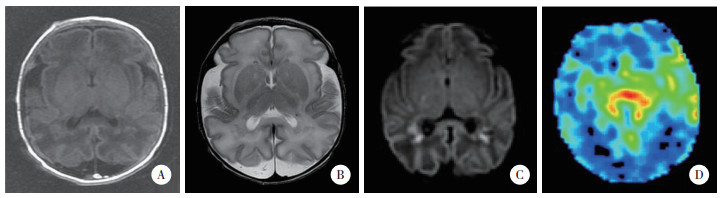

2 结果 2.1 3组ASL磁共振灌注成像检查结果所有患儿均获得满意图像。结果显示,轻度组中5例rCBF图像无显著变化,8例脑白质区灌注信号强度增高,见图 1。中度组中7例rCBF图像无显著变化,18例脑白质区灌注信号强度增高,11例脑灰质区灌注信号强度增高,14例基底节区和丘脑区灌注信号强度增高,见图 2。重度组中4例脑白质区灌注信号强度增高,3例脑灰质区灌注信号强度增高,2例基底节区灌注信号强度增高,2例丘脑内灌注信号强度增高,见图 3。

| A~C,常规MRI,双侧侧脑室旁可见斑片状短T1短T2信号影,弥散加权呈高信号;D,ASL,脑灰质区灌注信号强度增高. 图 2 中度组典型病例MRI及ASL图像 |